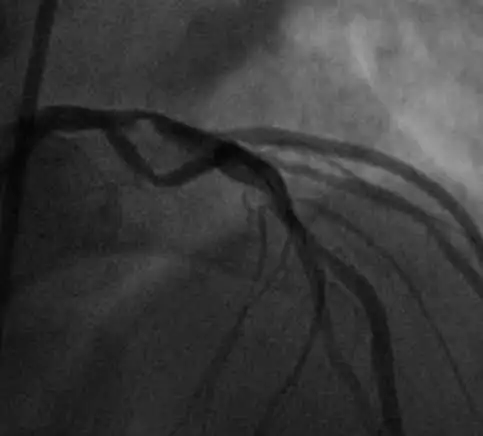

This patient was taken to the catheterization laboratory which revealed the following proximal LAD lesion. A drug-eluting stent was placed resulting in the restoration of normal flow. The patient should do well into the future.